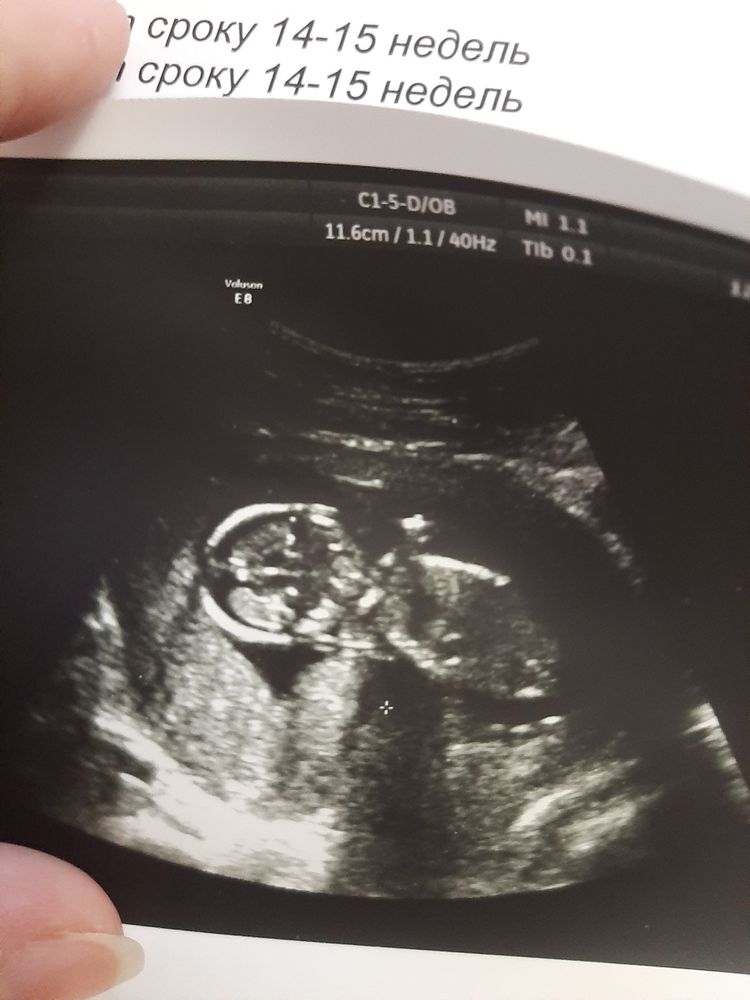

УЗИ 15 недель

Джу, ну в 12 пофиг. У меня 15 недель сейчас. Ну не судьба была вчера узнать пол ребёнка. Узнаю позже 😊

Разделяю ваше негодование. Пожалуй, на следующий раз я бы пошла в другое место делать УЗИ Одно вижу - тонус заметный. У меня так же сильно видно на фото (( только по передней стенке матки